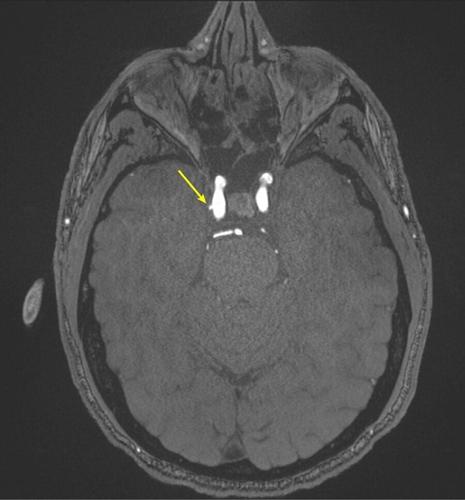

Representative axial time-of-flight MR angiography image in a 39-year-old male participant shows a laterally projecting intracranial aneurysm (arrow) originating from the right cavernous segment of the internal carotid artery. (RSNA via SWNS)

Aneurysm prevalence was greater in the high-exposure group (9.5%) compared to the low-exposure group (2.7%).

De Giorgi said: "Intracranial aneurysms were three times more common in highly exposed personnel.

"Even after accounting for other health factors such as age and blood pressure, the association remained significant.

Representative axial time-of-flight MR angiography image in a 35-year-old male participant shows a medially projecting intracranial aneurysm (arrow) originating from the right cavernous segment of the internal carotid artery. (RSNA via SWNS)

"These findings suggest that repeated blast exposure may leave a measurable vascular signature in the brain."